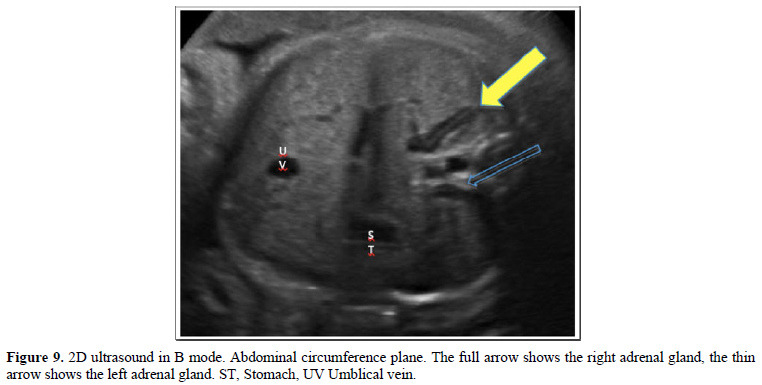

With the patient in the supine position, with the trunk above 30º approximately, the ultrasound evaluation was started according to the ISUOG-AIUM guidelines [24-26], and in compliance with the institutional protocol. After biometry and fetal morphological evaluation, FAG was evaluated in the axial plane, which was identified as a spindle-shape, long linear, echogenic image, with an anechoic halo located on the renal silhouettes, on the side and side of the spine, in the middle of the imaginary triangles formed by the inferior vena cava, the vertebral body and the hepatic angle for the right and for the left the triangle formed by the abdominal aorta, the vertebral body and the splenic angle with the visualization of the gastric chamber, in a plane superior to the measurement of the abdominal circumference [25,26] as described by Nyberg [27]. For the longitudinal plane, the adrenal glands were identified on the respective left and right renal pole, in the renal longitudinal section following the plane of the spine. After identifying and with the dual image, one for the axial plane and the other for the longitudinal plane, we proceed to calculate the volume of the FAG using the ellipse formula: longitudinal diameter x anteroposterior diameter x transverse diameter x 0.523. Same procedure for the contralateral adrenal gland.

This study has generated a nomogram of the volume of the FAG for a Latin-American population, which has specific differences from some reports in the literature (Figures 9 and 10).